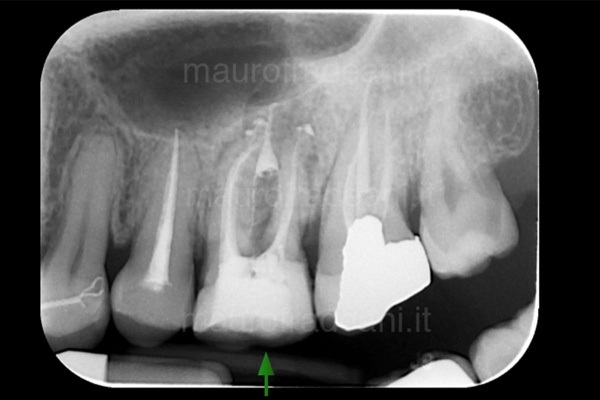

1/2: The patient presents severe pain and a swollen cheek sensation; the X-ray shows an apical lesion (the dark shadow under the root) of the first lower left molar. A Root canal therapy to devitalize the tooth is necessary.

2/2: The X-ray taken 6 months after the surgery shows a marked improvement in the dark area under the root, which has now disappeared. The symptoms complained of by the patient have never occurred again.